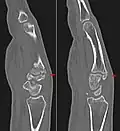

Carpal boss in CT. Carpal boss in CT.

Carpometacarpal boss is uncommon and there is not much scientific data. Its etiology has yet to be fully defined, but can be congenital in the form of an accessory ossicle (os styloideum) or may be acquired from trauma, repetitive use, or degenerative osteophytosis.[3] The condition usually begins to show in the 3rd or 4th decade.